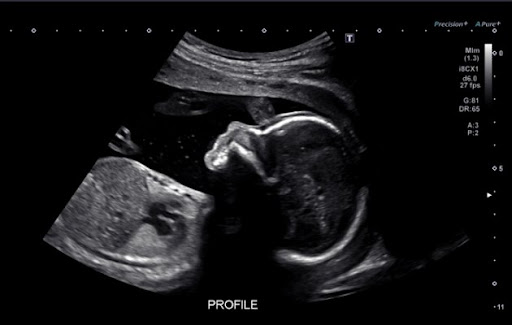

Ultrasound Images Of A Normal Fetus A And A Fetus With Trisomy 21 B Download Scientific Diagram